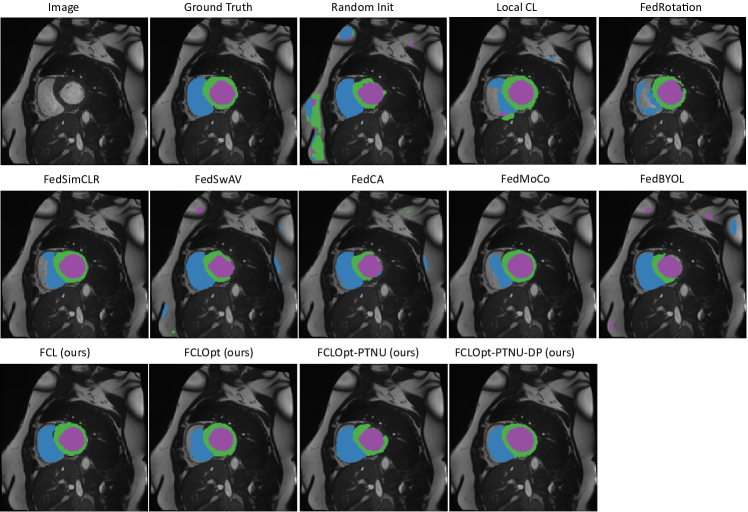

V-H Visualization

We visualize the segmentation results of the ACDC dataset in Fig. 4. The input image and the ground truth annotations are shown in the first two images, followed by segmentation results of the baseline methods, and the results of our methods are shown in the third row. Our methods generate better visual segmentation results than the baselines and are more similar to the ground-truth annotations, which are consistent with the quantitative results.